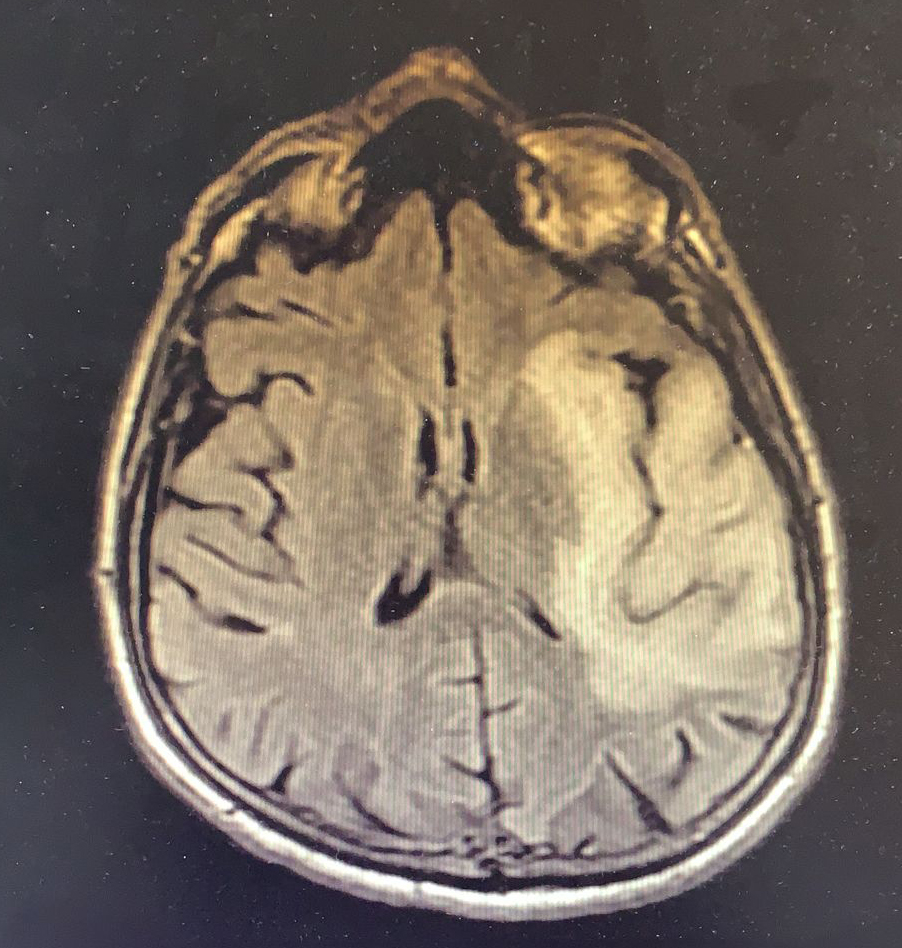

Elli dört yaşında HIV enfeksiyonu tanısıyla bir aydır antiretroviral tedavi (ART) alan erkek hasta, bir haftadır devam eden ateş yüksekliği, üşüme, titreme, bulantı, kusma, iştahsızlık yakınmaları ile kliniğimize başvurdu. FM’de genel durumu orta, şuuru açık, uykuya meyilli, oryante-koopere ve Glaskow koma skalası (GKS) 15 idi. Meningeal irritasyon bulguları negatifti. Dinlemekle solunum sesleri sağ bazalde azalmıştı ve bilateral orta zonda ralleri mevcuttu. Laboratuvarda lökosit sayısı 13.100/uL (%79 PNL) ve CRP 143 mg/L (<5 mg/L), HIV-RNA 718 kopya/ml, CD4 T lenfosit sayısı 126 /mm3 olarak belirlendi. Diğer kan tetkikleri normaldi. Hastanın kontrastlı kranial MR görüntülemesinde sol medial temporal lob düzeyinde, insular kortekste FLAIR sekansta ve diffüzyon ağrılıklı serilerde hiperintens sinyal değişiklikleri izlendi. Sol hipokampusta insüler kortekste kortikal ödem eşlik etmekte olup, her iki singulat girus düzeyinde korteks boyunca lineer difüzyon parlaklığı izlendi (Resim 1). Hastanın beyin omurilik sıvısında (BOS) incelemesinde hücre görülmedi. BOS kültüründe üreme olmadı, mikobakteri-PCR ve viral-bakteriyel menenjit paneli negatif idi.

Tedavinin ikinci ayında hasta kliniğimize yaklaşık iki haftadır olan konuşma bozukluğu yakınması ile başvurdu. Fizik muayende genel durumu iyi, şuuru açık, konuşması afazikti. Basit ve tekli emirleri yerine getirebiliyordu. GKS 15 olan hastada sağ kol ve bacakta kas gücü 4/5 idi, duyu defisiti saptanmadı. Yapılan kontrastlı kranial görüntüleme bir önceki kranial MRG tetkiki ile kıyaslandığında eski tetkikte lezyonun insular korteksle sınırlı olduğu güncel incelemede ise kısa sürede belirgin progresif değişiklikler geliştiği şeklinde raporlandı (Resim 2).